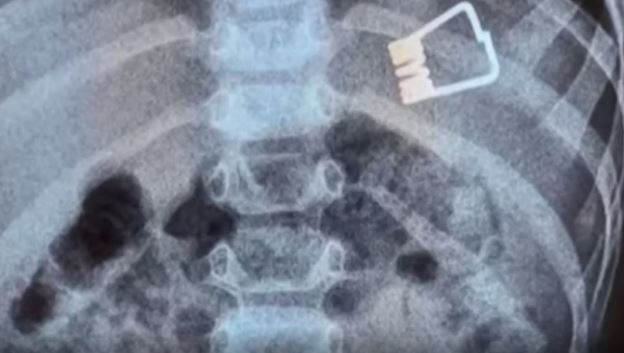

«Το παιδί κατάπιε τον συνδετήρα από το μανταλάκι που κατέληξε στο στομάχι του και όχι στα πνευμόνια» εξήγησε ο γιατρός και πρόσθεσε τα εξής:

«Η επέμβαση έγινε ενδοσκοπικά και με τη χρήση μιας μικρής μπασκέτας, το αντικείμενο εγκλωβίστηκε σε αυτήν και βγήκε».